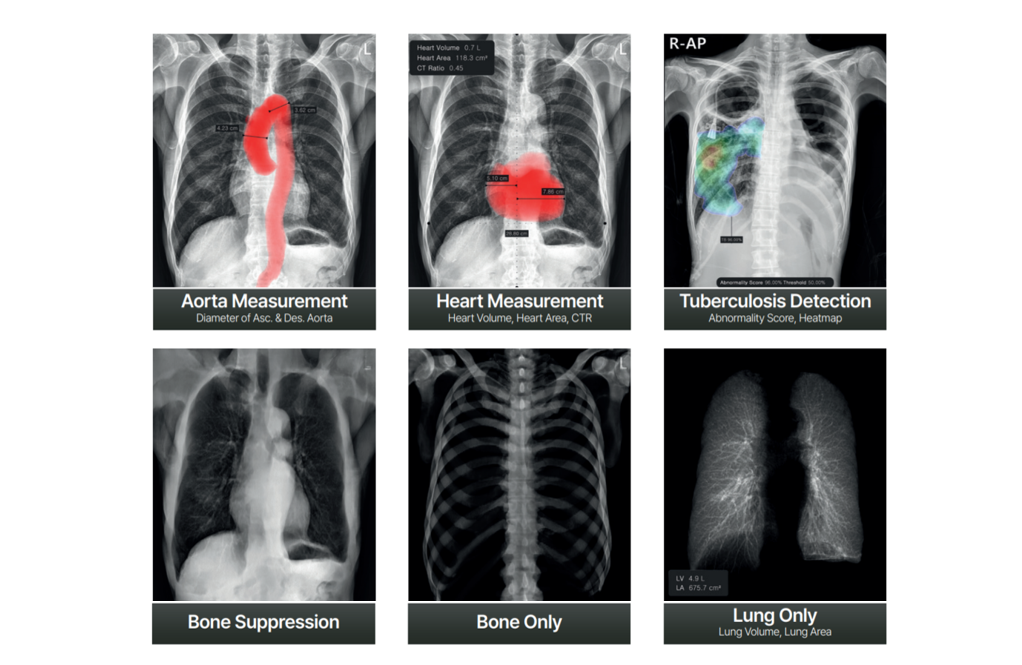

Founded in 1992 with a commitment to enhancing public health and advancing the medical industry, DK Medical Systems Co., Ltd. specializes in manufacturing high-quality, Korean-made radiology equipment, including digital X-ray systems. We prioritize customer satisfaction, listening carefully to client needs while upholding trust and integrity. Our extensive product lineup spans high-end to entry-level models, addressing various market demands and covering advanced diagnostic and radiotherapy equipment through our affiliates.